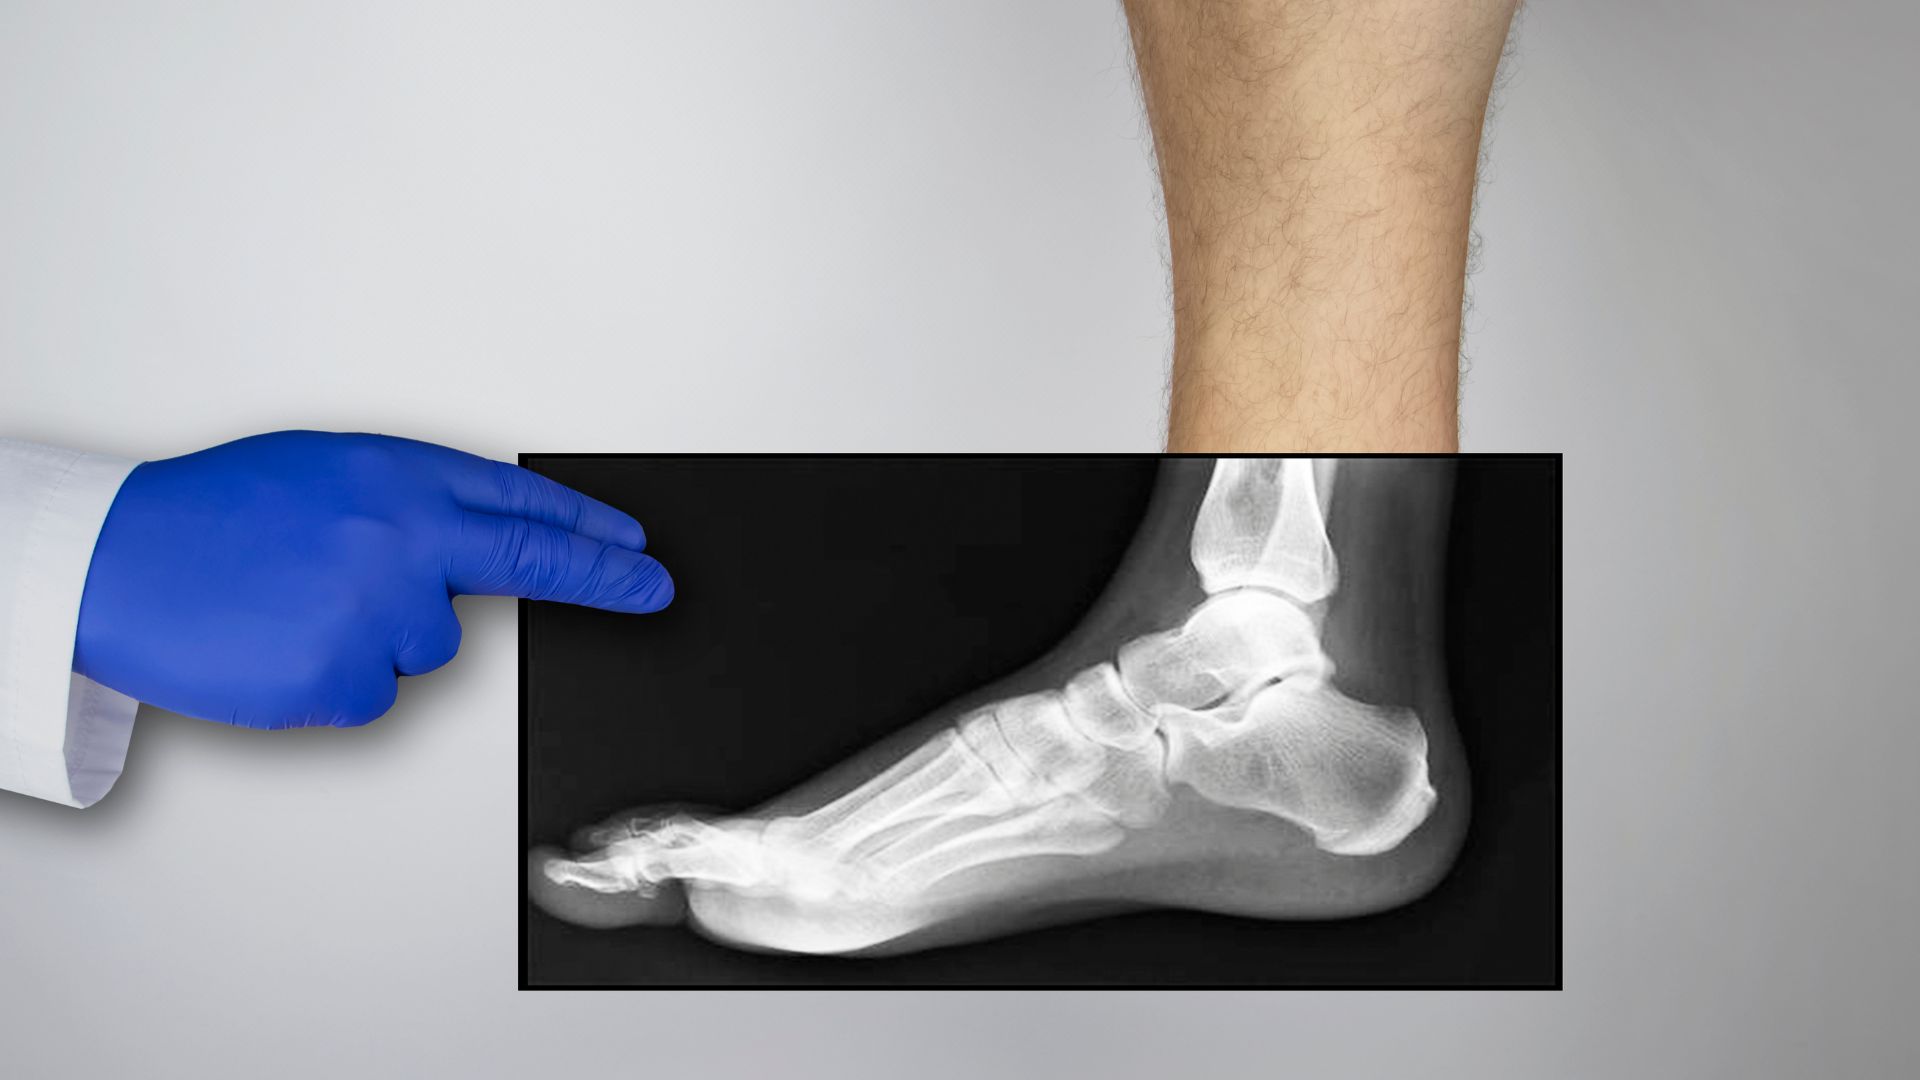

Kỹ thuật viên sẽ hướng dẫn người bệnh đặt bàn chân đúng tư thế theo yêu cầu chuyên môn, phổ biến gồm tư thế thẳng (AP) và nghiêng (lateral), có thể bổ sung tư thế chếch nếu cần khảo sát rõ hơn các xương nhỏ. Trong quá trình phát tia X, người bệnh cần giữ yên vị trí trong vài giây để đảm bảo hình ảnh sắc nét và hạn chế phải chụp lại.

Sau khi chụp, hình ảnh được truyền tới hệ thống lưu trữ và chuyển cho bác sĩ chẩn đoán hình ảnh phân tích. Bác sĩ sẽ đánh giá cấu trúc xương, khe khớp và các dấu hiệu bất thường trước khi trả kết quả. Toàn bộ quy trình thường diễn ra nhanh chóng và người bệnh có thể sinh hoạt bình thường ngay sau đó.